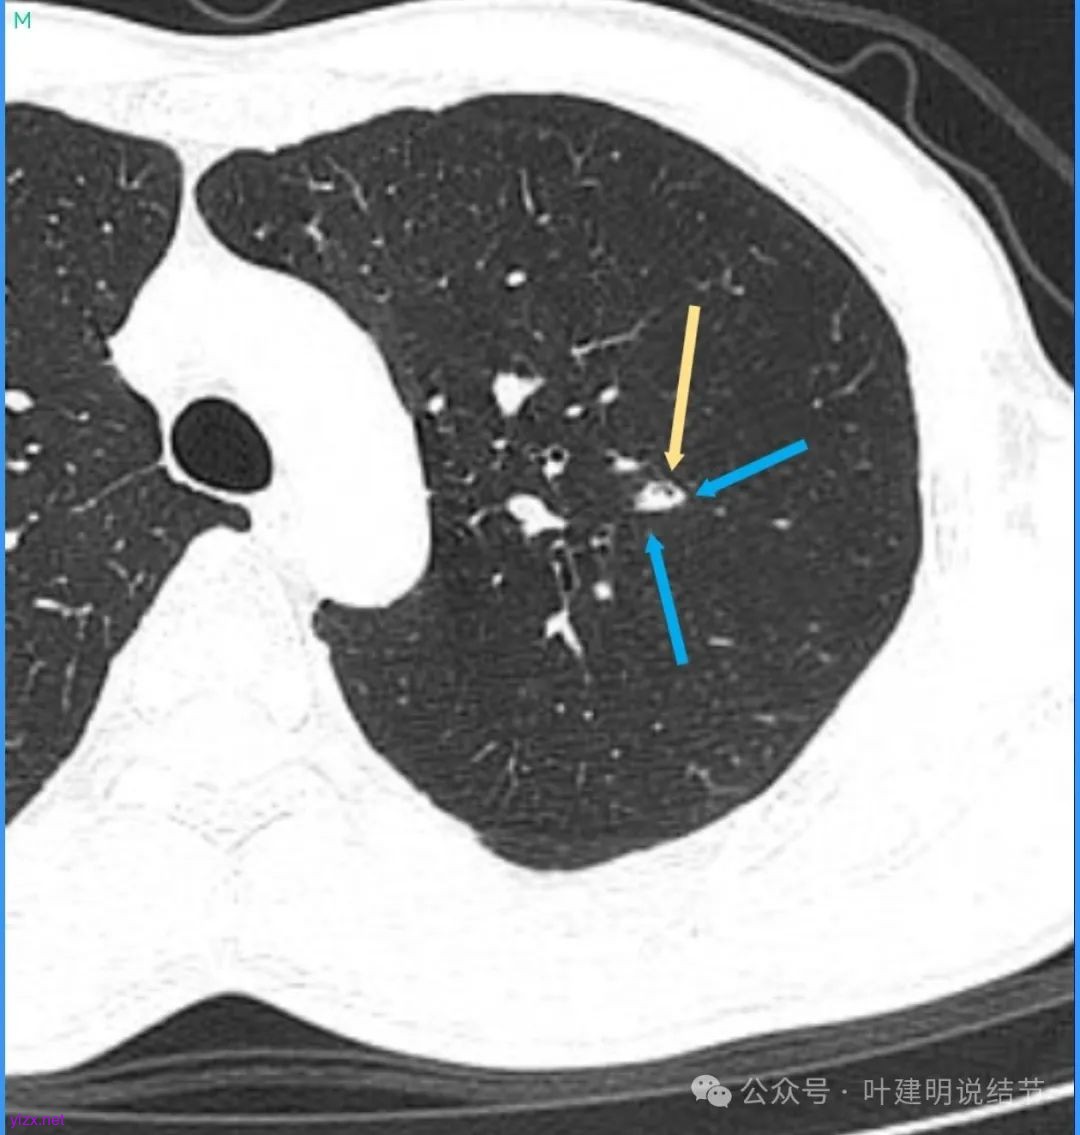

蓝色部分似乎是血管,但似乎又是增厚的支气管壁,局部细支气管扩张。

特别上上图边缘些的层面,蓝色箭头所指的实性明显又像位于扩张细支气管内或与支气管壁一块的样子。

再看看近半年前2024年11月时的影像:

我们发现一是病灶与25年3月的几乎没有区别,二是原来蓝色箭头处不太像血管,而是结节边缘的一部分,而结节灶内又是有扩张支气管的。